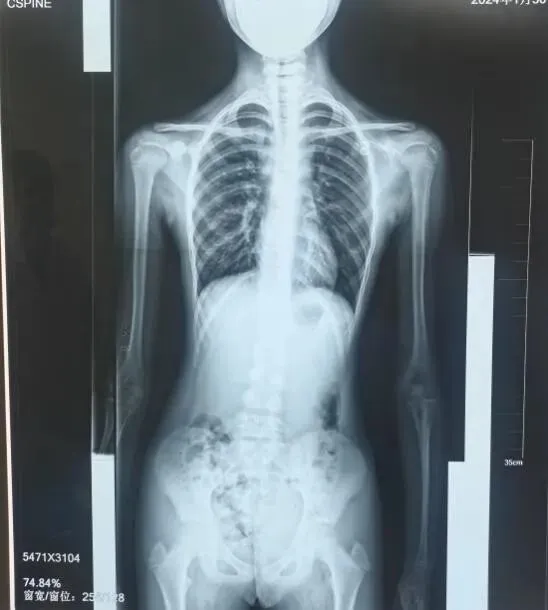

既往训练效果

治疗前

治疗后